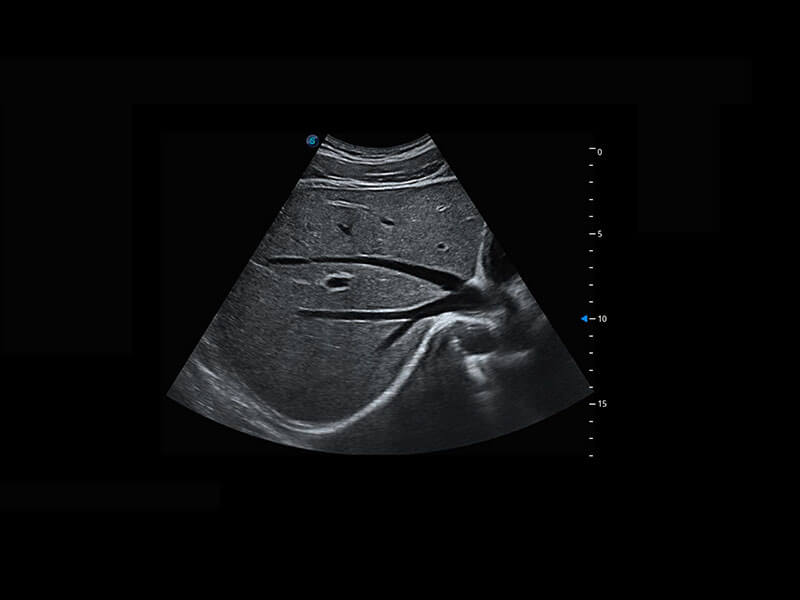

P60在胎兒早孕期超聲篩查中為您帶來優(yōu)異的圖像質(zhì)量。

早孕-胎心

高分辨率容積成像-早孕胎兒

胎兒體循環(huán)

光影成像-孕囊